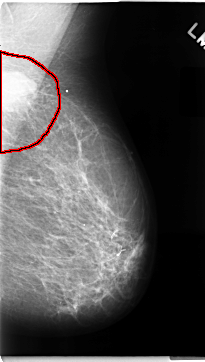

C_0072_1.LEFT_MLO

LEFT_MLO LINES 4696 PIXELS_PER_LINE 2664 BITS_PER_PIXEL 12 RESOLUTION 50 OVERLAY

FILE: C_0072_1.LEFT_MLO.OVERLAY

TOTAL_ABNORMALITIES 1

ABNORMALITY 1

LESION_TYPE MASS SHAPE LOBULATED MARGINS MICROLOBULATED

ASSESSMENT 5

SUBTLETY 5

PATHOLOGY MALIGNANT

TOTAL_OUTLINES 1

BOUNDARY